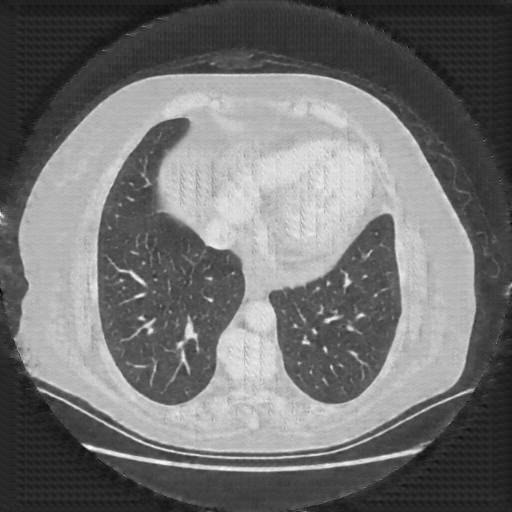

Reconstructed NATIVE CT scan (cycle consistency)

No window - Raw intensity values

Lung window (WL -600, WW 1500 β†’ Low βˆ’1350, High +150)

Mediastinum window (WL 40, WW 400 β†’ Low βˆ’160, High +240)